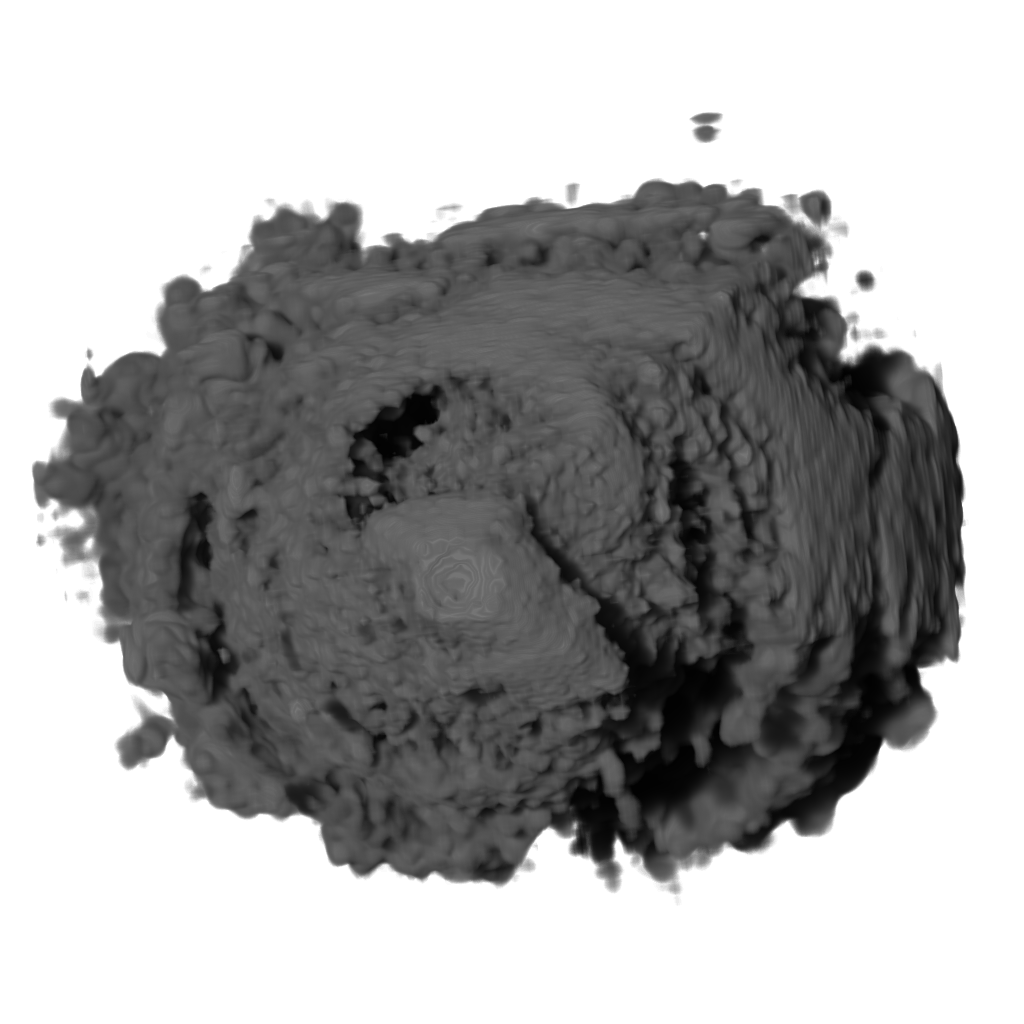

Recent works show that global illumination models based on gradient-free methods are suitable for rendering ultrasound volumes Ropinski10 ; solteszova10 . Ropinski et al. described a volumetric lighting model which simulates scattering and shadowing Ropinski10 . They use slice-based volume rendering from the view of the light source to calculate a light volume and raycasting to render the final image (see Figure 7b). A perceptual evaluation of the generated images indicates, that the proposed model yields stronger depth cues than gradient-based shading. Šoltészová et al. presented a single-pass method for simulation of light scattering in volumes solteszova10 . Light transport is approximated using a tilted cone-shaped function which leaves elliptic footprints in the opacity buffer during slice-based volume rendering. They use a slice-based renderer with an additional opacity buffer. This buffer is incrementally blurred with an elliptical kernel, and the algorithm generates a high-quality soft-shadowing effect (see Figure 7c). The light position and direction can be interactively modified. While these two techniques have been explicitly applied to 3D US data, the application of other volumetric illumination models potentially also improves the visual interpretation of 3D US data. Figure 8 shows a comparison of six different shading techniques as applied to a 3D US scan of a human heart. While the first row of Figure 8 shows examples for the already addressed shading techniques, the second row shows three alternative approaches. Figure 8d incorporates scattering of light in volume data, as proposed by Kniss et al. kniss02halfangle . Their slicing technique allows textured slices to be rendered from both light and viewing direction simultaneously. By sampling the incident light from multiple directions while updating the light’s attenuation map, they account for scattering effects in slice-based volume rendering. Figure 8e shows the application of the directional occlusion shading technique schott09directionalocclusion . This technique constrain the light source position to coincide with the view point. Finally, Figure 8f shows the application of a technique based on spherical harmonic lighting lindemann10materials .